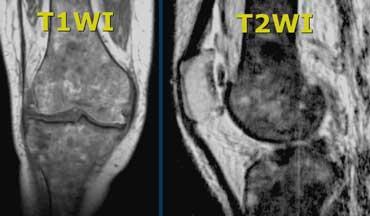

Tủy xương bình thường và bất thường

Ở người trưởng thành, tủy xương chủ yếu được cấu tạo bởi mô mỡ.

Các đảo tủy đỏ bình thường có thể tạo ra hình ảnh dễ gây nhầm lẫn.

Tủy đỏ có thể nổi bật ở phụ nữ trẻ, người hút thuốc lá, người sống ở vùng cao, bệnh nhân mắc bệnh huyết sắc tố, hoặc không rõ nguyên nhân.

Miễn là đáp ứng đủ các tiêu chí ở bên trái, đây vẫn được coi là bình thường.

Tủy đỏ bình thường ở hình bên trái.

Giới hạn trong vùng hành xương, không lan vào vùng đầu xương.

Xuất hiện dưới dạng các đảo tủy.

Trên chuỗi xung T1W có tín hiệu sáng hơn cơ.

Tủy xương bất thường

Ca lâm sàng bên trái cho thấy tủy xương bất thường.

Trên chuỗi xung T1W, cường độ tín hiệu thấp hơn cơ.

Trên chuỗi xung T2W, tín hiệu rất sáng.

Tín hiệu bất thường lan vào vùng đầu xương.

Một ca lâm sàng khác với tủy xương bất thường.

Trong trường hợp này, tủy xương giảm tín hiệu quá mức trên cả T1 và T2 do lắng đọng sắt trong tủy sau nhiều lần truyền máu ở bệnh nhân mắc bệnh hemosiderosis (ứ sắt).